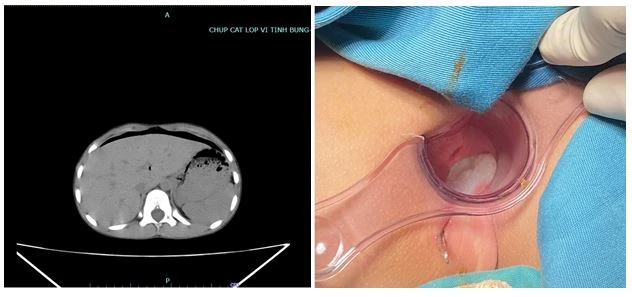

Bệnh nhi được phẫu thuật khâu vết thương 2 mặt trực tràng, xử lý vết thương vùng tầng sinh môn, đồng thời rửa trực tràng.

Sau đó, các bác sĩ tiến hành phẫu thuật nội soi ổ bụng, thấy có vết thương đi ra mặt sau bàng quang, đâm thủng phúc mạc. Bệnh nhi được rửa ổ bụng, đặt dẫn lưu qua hậu môn.